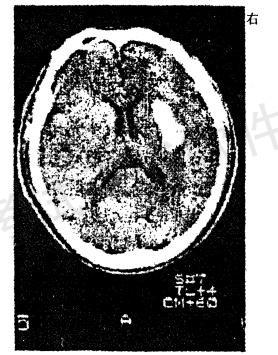

问题 男性,56岁。高血压患者。旅游登山中突然左侧 肢体发麻、乏力。急送医院,摄头颅CT片如图 最可能的诊断是

选项 A.脑出血 B.脑血栓形成 C.蛛网膜下腔出血 D.脑栓塞 E.短暂脑缺血发作

答案 A